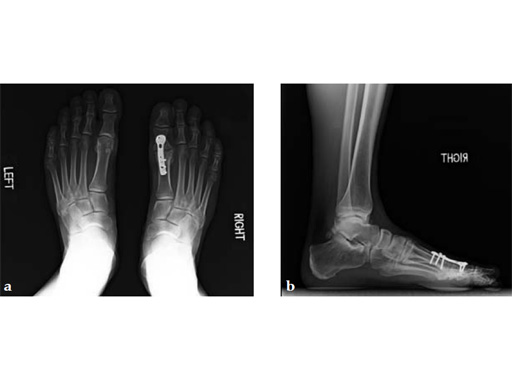

Case 1: First MP fusion VA-LCP

A 57-year-old woman has suffered rheumatoid arthritis for several years. She presented with pain and deformity in the left forefoot moreso than in the right. Clinical examination reveals severe hallux valgus deformity and dislocation of MP joints 11 through V, with synovitis.

Case provided by Juan Bernardo Gerstner, Cali, Columbia

A dorsal transtendinous approach was used and reaming of the first MT head and basal articular surface of the proximal phalanx was performed with the new reamers (see Fig. 3a-b).

A left MP fusion was performed as well as a II to V MT head resection arthroplasty, and fixed with K-wires for 4 weeks (see Fig. 4a-b). The patient was weight bearing immediately with wooden shoes and K-wires were removed 4 weeks postoperatively.